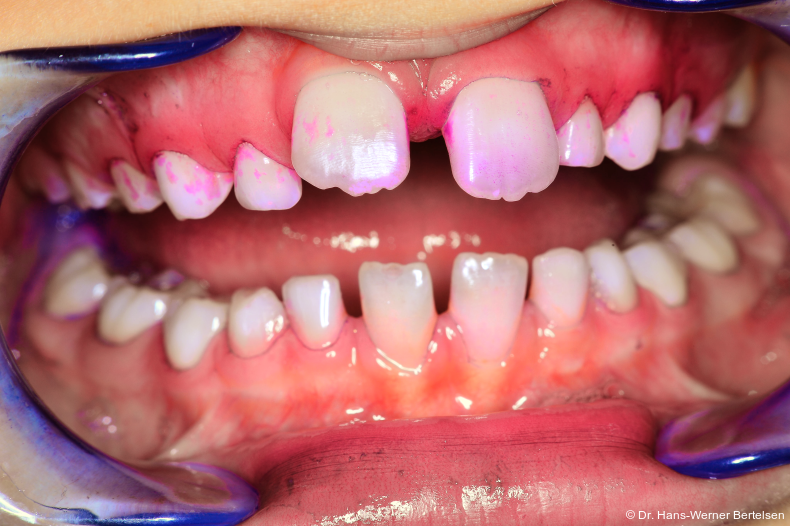

Erst die fotografische Dokumentation des Mundhygienestatus brachte den entscheidenden Durchbruch. „One size fits all“, das bekannte Prädikat aus dem stationären Sockenhandel, trifft in der Zahnarztpraxis leider bekanntlich nicht zu. In Bezug auf die Compliance der so wichtigen Anleitung der Zahnpflege kommen wir in unserer ­Praxis mit der hier beschriebenen Technik doch sehr nahe an eine 100%ige Quote heran. Es ist jedes Mal aufs Neue spannend und faszinierend, wenn sich bereits achtjährige Kinder darauf freuen, ihre erlernten Putzerfolge in der Praxis vorzuführen, um dann am Monitor gemeinsam mit der ZMF oder mir ihre tollen Ergebnisse zu bestaunen. Mitarbeit, Selbstwirksamkeit und Lob sind Garanten für eine gelungene Prävention und ersetzen Ermahnung, Frustration und Unverständnis.

Ein Bild sagt mehr als tausend Worte

Wie im Leben, so auch hier - die Fotodokumentation erspart uns nach einfacher Implementierung in den Verlauf der Prophy­laxe sehr viel Zeit. Zeit, die wir mit allen vorherig angewandten anderen Mitteln und Techniken regelmäßig vergeudet hatten. Aber es gibt noch weitaus mehr Vorteile, sowohl für die Praxis als auch für die Kinder und Eltern. So lässt sich die Motivation für einen Folgetermin durch die Ankündigung eines weiteren Fototermins sehr gut erlangen. Gleichzeitig steigt bei einer sichtbar nachgewiesenen Verbesserung der Zahnpflege mit der Laune auch der Ehrgeiz unserer kleinen Patient/-innen, uns bei Folgeterminen wieder mit einem guten Ergebnis zu überzeugen. Sehr selten nur beobachten wir an dem Folgetermin einen Rückschritt. Das einmal erzielte Putzergebnis erweist sich in der Regel als erlernt und damit sehr stabil. Zudem ist es die beste Gelegenheit, für den Einsatz von Plaque-Färbe­tabletten zu werben. Es ist schon erstaunlich, wie wenig An­wendung dieses wertvolle und aus meiner Sicht schier un­verzichtbare Hilfsmittel in der Bevölkerung findet. Die Ver­fügbarkeit von Plaque-Färbetabletten ist in der Lernphase sehr viel wichtiger als die Marke der Zahnpasta.